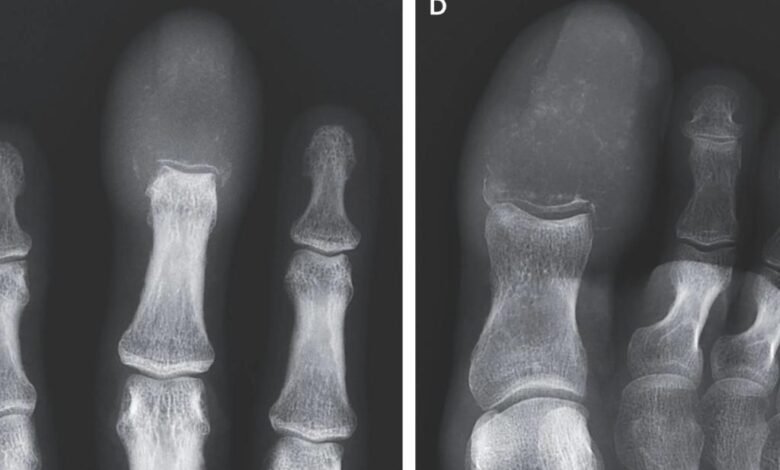

Las grotescas imágenes de rayos X muestran hueso completamente devorado por tumores destructivos.

Pero las radiografías revelaron la verdad aterradora: ambos huesos fueron borrados por lesiones líticas, con tumores que reemplazan completamente la estructura ósea en las puntas del dedo y el dedo del pie.